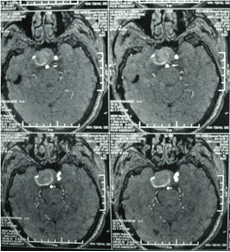

經(jīng)顱多普勒

頸內(nèi)動脈虹吸段巨大動脈瘤(約3cm ×3cm

顱內(nèi)動脈瘤是指腦動脈的局部性異常擴大,多在腦底動脈的分叉處或分支的夾角向外突出,多呈囊狀。TCD對顱內(nèi)動脈瘤的總檢出率為67 %,動脈瘤>1cm的檢出率為82 %。TC D 對較大動脈瘤的檢測有其特征性表現(xiàn),其典型表現(xiàn)為:瘤體內(nèi)血流速度明顯低于載瘤動脈血流速度,其收縮峰陡峭或多峰不整,舒張期末流速極低或斷流,PI 值增高,多為雙向血流,聲頻低鈍,似撞擊樣轟鳴音。